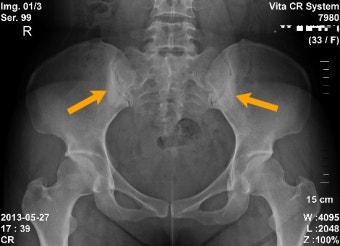

- X-ray: 천장관절 이상 확인

| 엉덩이·골반 통증 | 천장관절염 증상, 한쪽 또는 양쪽 반복 |